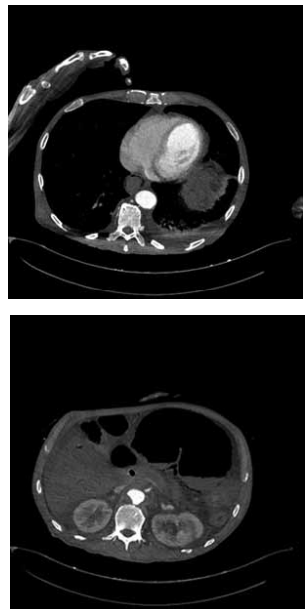

Paciente de 78 anos, hipertenso, tabagista, é admitido no

pronto-socorro em choque séptico de instalação rápida,

associado à dor abdominal súbita e distensão. Realizada

tomografia computadorizada de abdome a seguir:

Qual o diagnóstico mais provável baseado na interpretação da imagem e no quadro clínico?